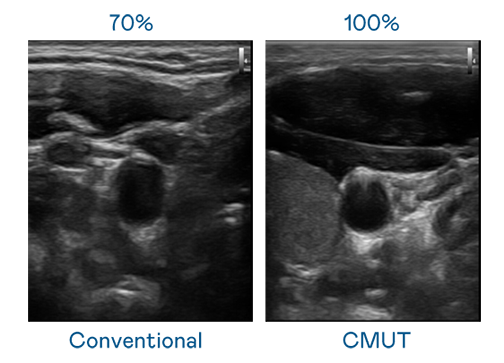

CMUT 技术是一种用电容式微机电元件来产生超音波讯号的技术。与传统 PZT 压电式技术相比,CMUT 频宽增加 30%,更宽频的超音波讯号让影像解析度大幅提升,是实现高影像品质医疗超音波扫描、促进精准医疗发展的关键技术。

超音波影像的解析度高低,首先取决于探头能发出的讯号频宽。壹定发 CMUT 可提供高清晰的超音波讯号,提供高频宽、高灵敏度、影像纹理细节更高的超音波影像,协助医护人员缩短影像判读时间及利用精准的医疗影像进行诊断。